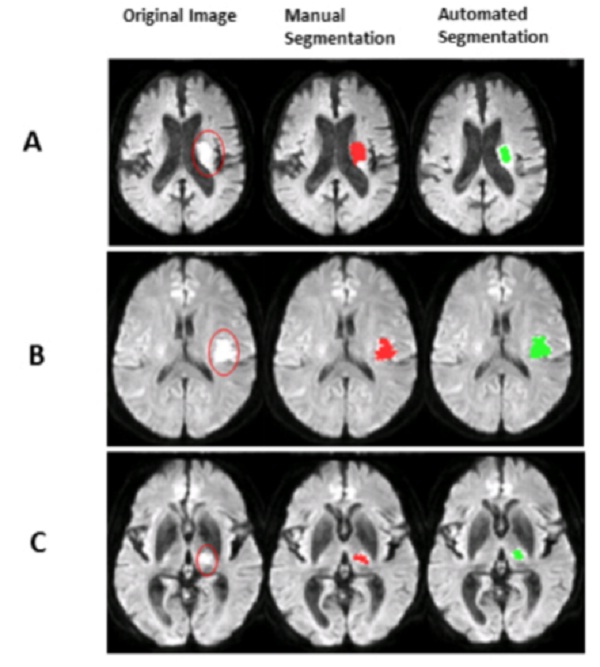

Vấn đề với phân đoạn tổn thương thủ công là nó cực kỳ tốn thời gian và sự sai lệch của người vận hành. Thực tế, những sai lầm đã xảy ra - đôi khi đột quỵ được chẩn đoán là tình trạng không đột quỵ. Tuy nhiên, các nhà khoa học từ Trung tâm PET của Đại học Turku và Turku giới thiệu một công nghệ dựa trên AI, có thể cải thiện độ chính xác và thời gian của phânVề cơ bản, đây là một hệ thống tự động, có thể xem qua các hình ảnh cộng hưởng từ, phân tích các hình ảnh đó và phân loại các tổn thương AIS thành các trường hợp đột quỵ và không đột quỵ. Hệ thống này thực sự khá phức tạp. Nó so sánh các hình ảnh có trọng số khuếch tán (DWIs) và hình ảnh hệ số khuếch tán rõ ràng (ADC) của não bệnh nhân và lưu các tổn thương tiềm tàng dưới dạng mặt nạ tổn thương. Sau đó, một bộ phân loại nhị phân được sử dụng để sàng lọc các mặt nạ đó để xác nhận xem các mặt nạ này có thực sự chứa các tổn thương AIS hay không. Hệ thống được đào tạo với khoảng 200 MRI. Kết quả là chẩn đoán nhanh, không sai lệch, có thể chính xác hơn so với chẩn đoán được cung cấp bởi phân đoạn tổn thương thủ công kiểu cũ.

Về cơ bản, đây là một hệ thống tự động, có thể xem qua các hình ảnh cộng hưởng từ, phân tích các hình ảnh đó và phân loại các tổn thương AIS thành các trường hợp đột quỵ và không đột quỵ. Hệ thống này thực sự khá phức tạp. Nó so sánh các hình ảnh có trọng số khuếch tán (DWIs) và hình ảnh hệ số khuếch tán rõ ràng (ADC) của não bệnh nhân và lưu các tổn thương tiềm tàng dưới dạng mặt nạ tổn thương. Sau đó, một bộ phân loại nhị phân được sử dụng để sàng lọc các mặt nạ đó để xác nhận xem các mặt nạ này có thực sự chứa các tổn thương AIS hay không. Hệ thống được đào tạo với khoảng 200 MRI. Kết quả là chẩn đoán nhanh, không sai lệch, có thể chính xác hơn so với chẩn đoán được cung cấp bởi phân đoạn tổn thương thủ công kiểu cũ.